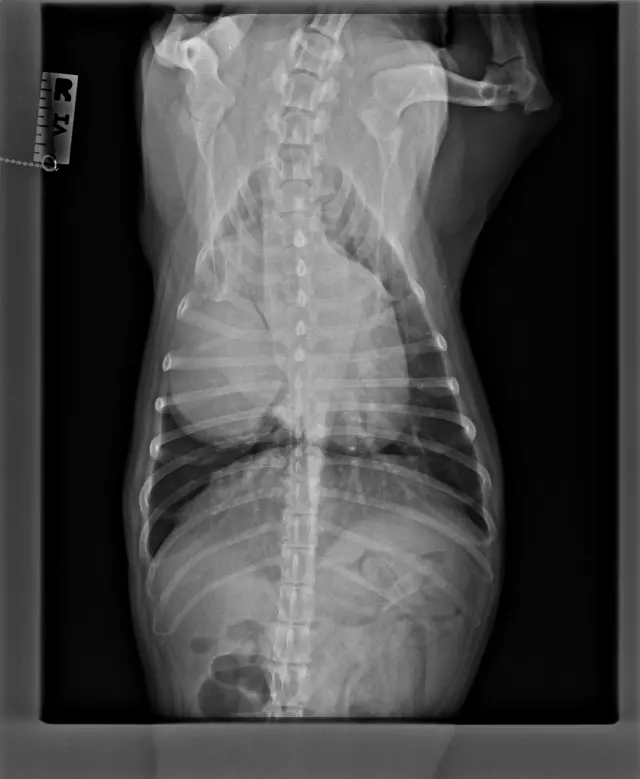

Tak a máme výsledky z CT a biopsie. CTčko nám ukázalo, že Bessie má nádor na pravom pľúcnom laloku o veľkosti 9,9 × 9 × 4,3 cm. Aktuálne jej tlači na zadnú dutú žilu, v dôsledku čoho jej už opúcha pečeň. Nádor je však jeden, solídny a žiadne ďalšie metastázy sa nepotvrdili. Čo však ukázala biopsia, je že nádor je zhubný a ide o primárny karcinóm pľúc.

Termín operácie mala 17. 11., kde jej operáciu mali na starosti MVDr. Valášek a MVDr. Valašek Nusová. Nás čakali najťažsie hodiny, kedy sme len čakali na telefónat z VetPointu. Nakoniec operácia trvala až 2,5 hodiny, nádor odo dňa kedy sa robilo CT, narástol na 10×9,5×5 cm, čo nám len potvrdilo, že rástol extrémne rýchlo. Môžme povedať, že jej operácia zachránila život. Bessie bola na klinike hospitalizovaná do 19. 11. od kedy je v domácej liečbe. Pomaly sa zotavuje a zvláda to veľmi statočne. Prvá noc doma bola náročná, ale už sa z nej stáva opäť veselá Bessie, ktorá vôbec nekašle.